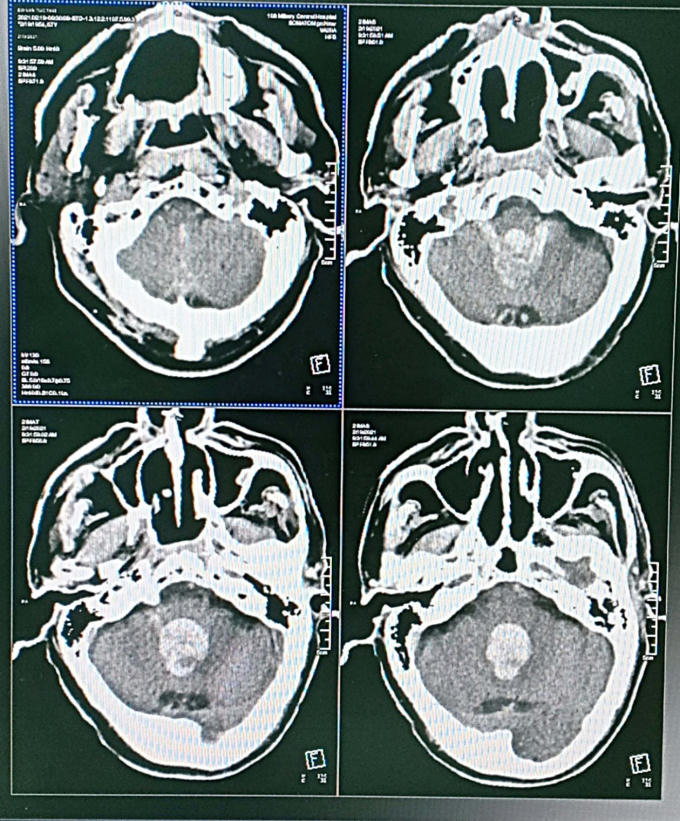

Hình ảnh máu tụ đóng thành khuôn trong não bệnh nhân. (Ảnh: vietnamnet)

Nam bệnh nhân tiên lượng tử vong 100% do máu chảy vào trong não thất đóng bánh lại thành khuôn không thể dẫn lưu ra ngoài.

Bác sĩ Nguyễn Thị Loan, Trung tâm Đột quỵ cho biết, trước đây những người bệnh chảy máu não thất lớn gây lụt hệ thống não thất như trường hợp này sẽ có tỷ lệ tử vong là 100%, do máu chảy vào trong não thất đóng bánh lại thành khuôn không thể dẫn lưu ra ngoài.